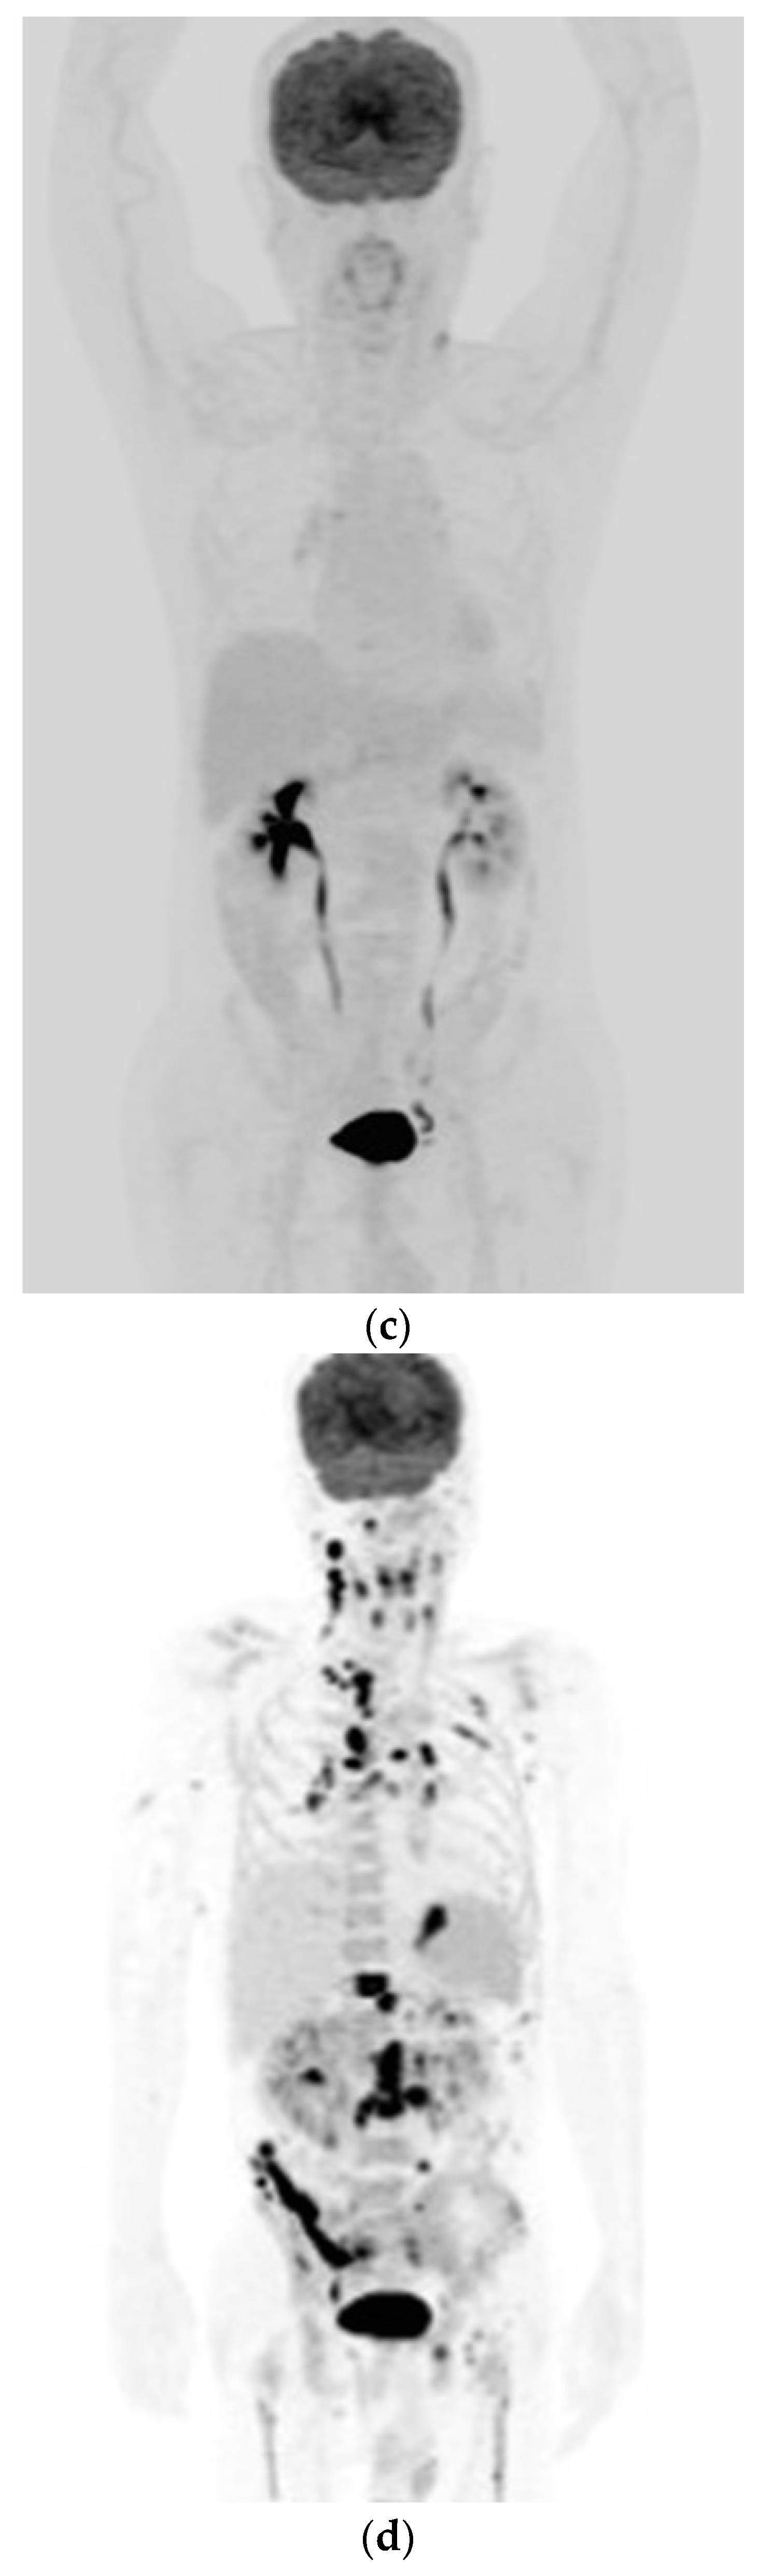

Evolution of 18F-FDG Uptake as a Pitfall of Image Diagnosis for Systemic Anaplastic Large Cell Lymphoma